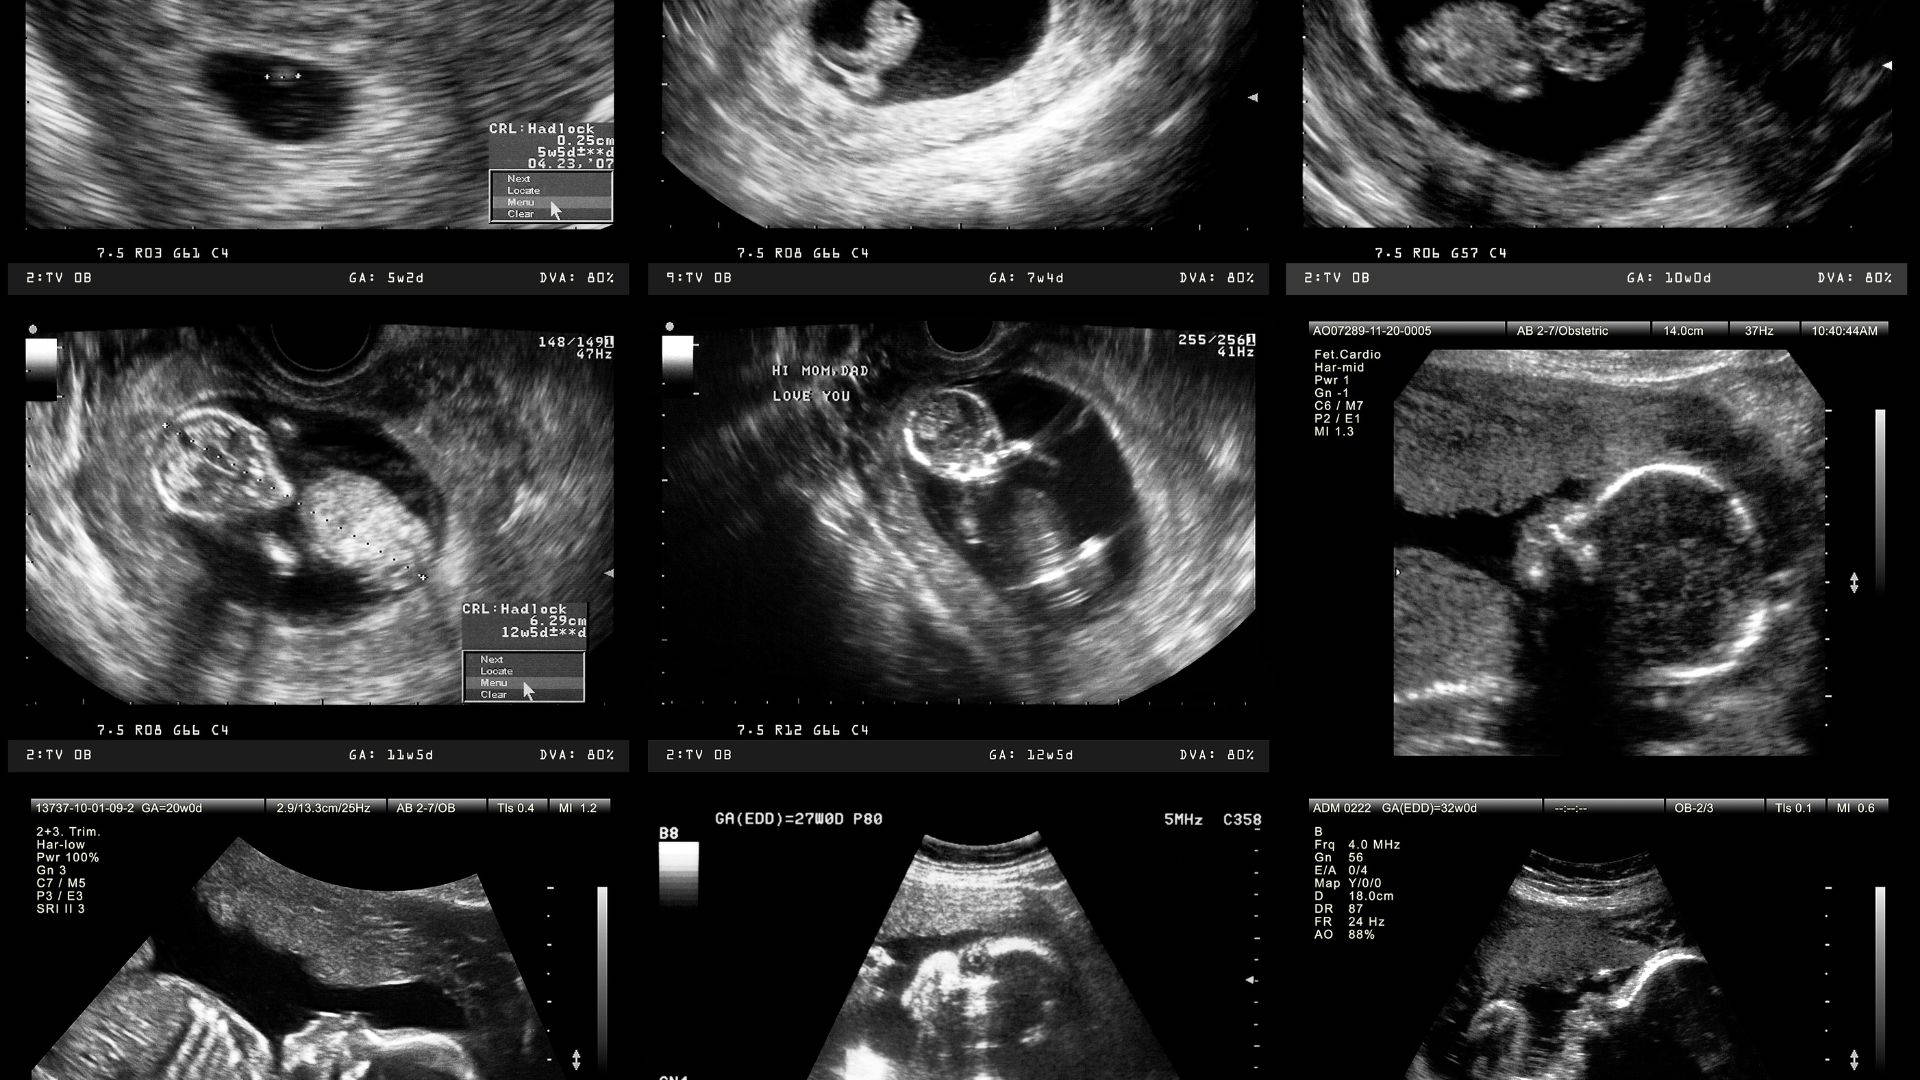

Dalam perkahwinan pertama, dia dikurniakan 4 orang sebagai penyeri hidup. Satu hari, anaknya yang berusia 10 tahun dimasukkan ke hospital atas isu kesihatan. Niatnya untuk menderma darah terbantut setelah disahkan keputusannya sebagai tidak serasi. Dari situ, si ayah mulai curiga dan terdetik melakukan ujian DNA. Alangkah terkejutnya, keempat-empat anaknya itu disahkan sebagai bukan anak kandung.

Si isteri menegaskan dirinya tidak pernah melakukan sebarang kecurangan, namun lelaki itu nekad untuk bercerai. Setelah 6 tahun menduda, dia akhirnya terbuka hati untuk berkahwin baru. Kali ini, dia dianugerahkan dengan seorang bayi lelaki. Kerana trauma lampau, dia melakukan ujian DNA sekali lagi. Apa yang mengejutkan, si kecil itu juga mempunyai DNA yang tidak sepadan dengannya. Saat itu, lelaki itu sempat mengalami tekanan mengenangkan ujian berat yang terpaksa ditanggungnya.

Namun, segala kejadian itu sebenarnya berpunca daripada fenomena Kembar Chimera. Ketika masih berada dalam rahim ibunya, lelaki tersebut dipercayai telah ‘menelan’ adik kembarnya sekeligus menyebabkan embrio mereka bergabung menjadi satu. Akibatnya, tubuh lelaki ini mengandungi 2 set DNA serta genetik yang berbeza. Inilah punca mengapa semua ujian DNA yang dijalankan terhadap 5 anaknya menunjukkan keputusan yang tidak sepadan.